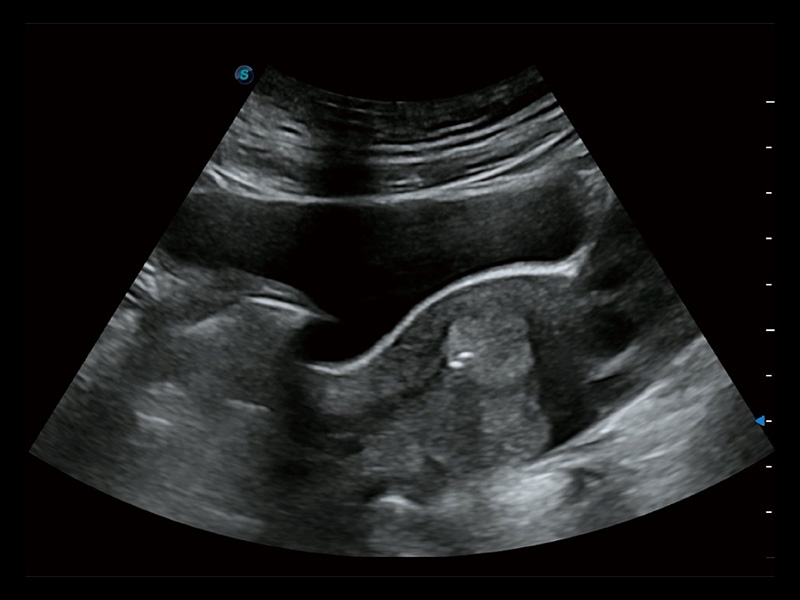

超声引导下胚胎移植

宫外孕血流